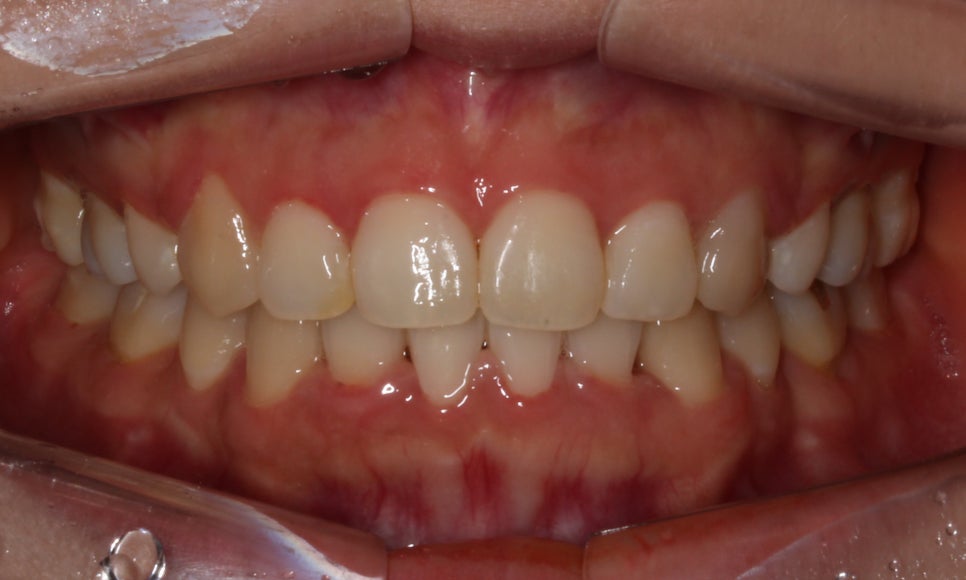

<14개월 교정이 끝난 후 모습>

교정이 끝난 모습입니다:-D

덧니교정일 경우에는 치아가 배열되면

겹쳐져 있던 치아가 제자리로 돌아오면서

블랙트라이앵글 (black triangle)이

생길 가능성이 높습니다.